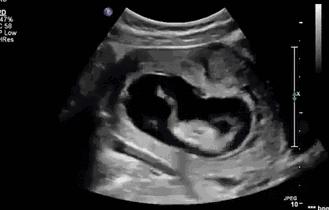

胎动是上苍赐给宝妈们的一份独特礼物,为此可以让宝妈真真实实的感觉到小生命的存在,在孕期不感到孤单。小宝宝早在孕7-8周间,就可以在B超下看到轻微的活动,但是这个轻微的活动不能有效冲击宫壁,从而不能被宝妈所感觉到。

那么问题来了,没有胎动就提示胎儿没有活动吗,回答是否定的,有胎动提示胎儿在活动,但有胎儿活动并不一定能被宝妈感知道胎动。也就是讲没胎动不等于宝宝没有动,很简单的一个例子,在四维下明显宝宝动的很欢,可是宝妈自己就是没有感觉到。这估计就是命吧,对胎动的敏感性太低,这类人不是一个两个的数量,而是很多个,或许宝妈你就是其中的一员。